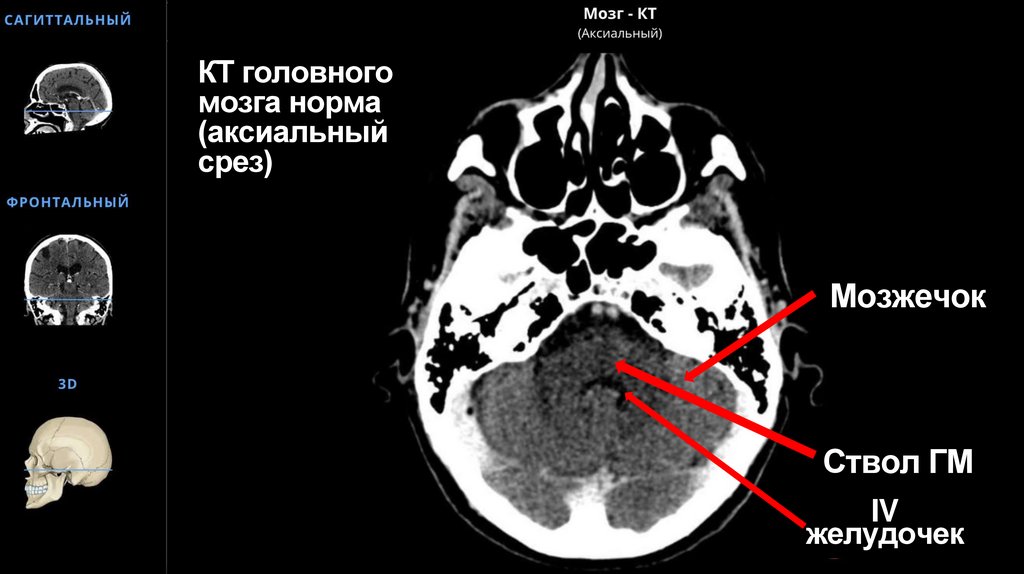

КТ головного мозга норма (аксиальный срез)

59. КТ головного мозга норма (аксиальный срез)

Мозжечок

Ствол ГМ

IV

желудочек